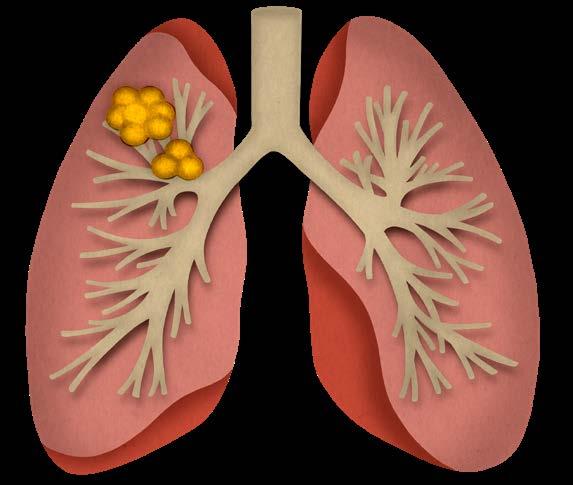

Mynd 6-1 Lítið lungnakrabbamein í hægra lunga (ör) sem fannst við skimun með tölvusneiðmyndum.

áttunda áratug síðustu aldar sýndu ekki fram á lækkun á dánartíðni borið saman við venjulegt eftirlit.1 Greindum tilfellum fjölgaði reyndar í skimunarhópi og fimm ára lifun batnaði en dánartíðni hélst óbreytt.

Með tilkomu tölvusneiðmyndatækni (TS) varð unnt að finna mun smærri hnúta í lungum en áður var mögulegt með hefðbundnum röntgenmyndum (mynd 6-1). Á síðustu áratugum hefur verið efnt til stórra framvirkra samstarfsverkefna, bæði í Bandaríkjunum og Evrópu. Fyrstu rannsóknir á skimun með TS voru gerðar í Japan og fyrsta alþjóðlega rannsóknin benti til þess að unnt væri að finna um